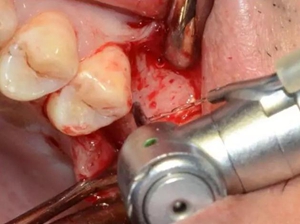

定點(diǎn)定向,初步擴(kuò)孔

使用止停環(huán)控制深度,逐級(jí)預(yù)備打開(kāi)嵴頂入路。探之竇膜力反饋正常,呈持續(xù)張力。手動(dòng)探查分離通路周圍竇粘膜并略提升。